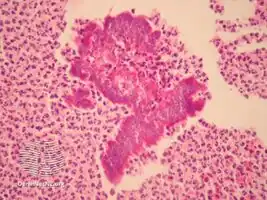

Botryomycosis